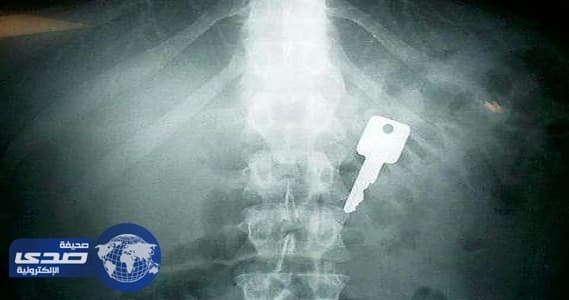

للأخطاء الطبية ضحايا كثر ،تشهد عليها العديد من مستشفيات المملكة ، والتي من أبرزها استخراج أجسام صلبة من أجساد مرضى مواطنين ومقيمين،كالشعر والملاعق والمسامير وأدوات جراحة أو كبسولات مخدرات.

و تعرض له مقيم هندي (24 عاماً)، حيث اخترق مسمار قلبه مرتداً من جهاز تثبيت آلي، وتمكن فريق طبي في مركز الأمير سلطان لجراحة القلب في القصيم من إنقاذ حياته، فيما ابتلعت مريضة وافدة ملعقة كادت تتسبب في وفاتها.